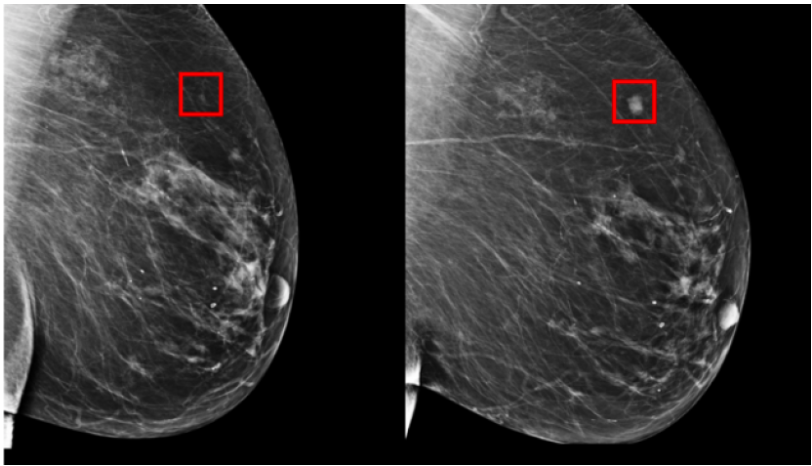

Ciudad de México, 08 Julio.- Un grupo de investigadores del Instituto de Tecnología de Massachusetts (MIT) crearon un modelo de aprendizaje que puede predecir el cáncer de mama hasta cinco años antes de que aparezca.

Regina Barzilay, autora principal del proyecto, destacó que esto fue posible gracias a un modelo capaz de aprender patrones de una mamografia que detalla cuales tejidos son precursores de tumores malignos.

Esto es un hito que hizo posible que en lugar de identificar estos patrones de manera manual, se pueda deducir el resultado directamente de los datos de más de 90 mil mamografías.

“Desde la década de 1960, los radiólogos han notado que las mujeres tienen patrones únicos y ampliamente variables de tejido mamario visibles en la mamografía”, explicó Constance Lehman.

Al ser probada esta técnica, se colocó con precisión al 31% de todas las pacientes con cáncer de mama en su categoría de mayor riesgo, en comparación con sólo el 18% de los modelos tradicionales.

Estos resultados son mejores para predecir el riesgo que los enfoques existentes, ya que los patrones son demasiado sutiles para que el ojo humano los detecte.